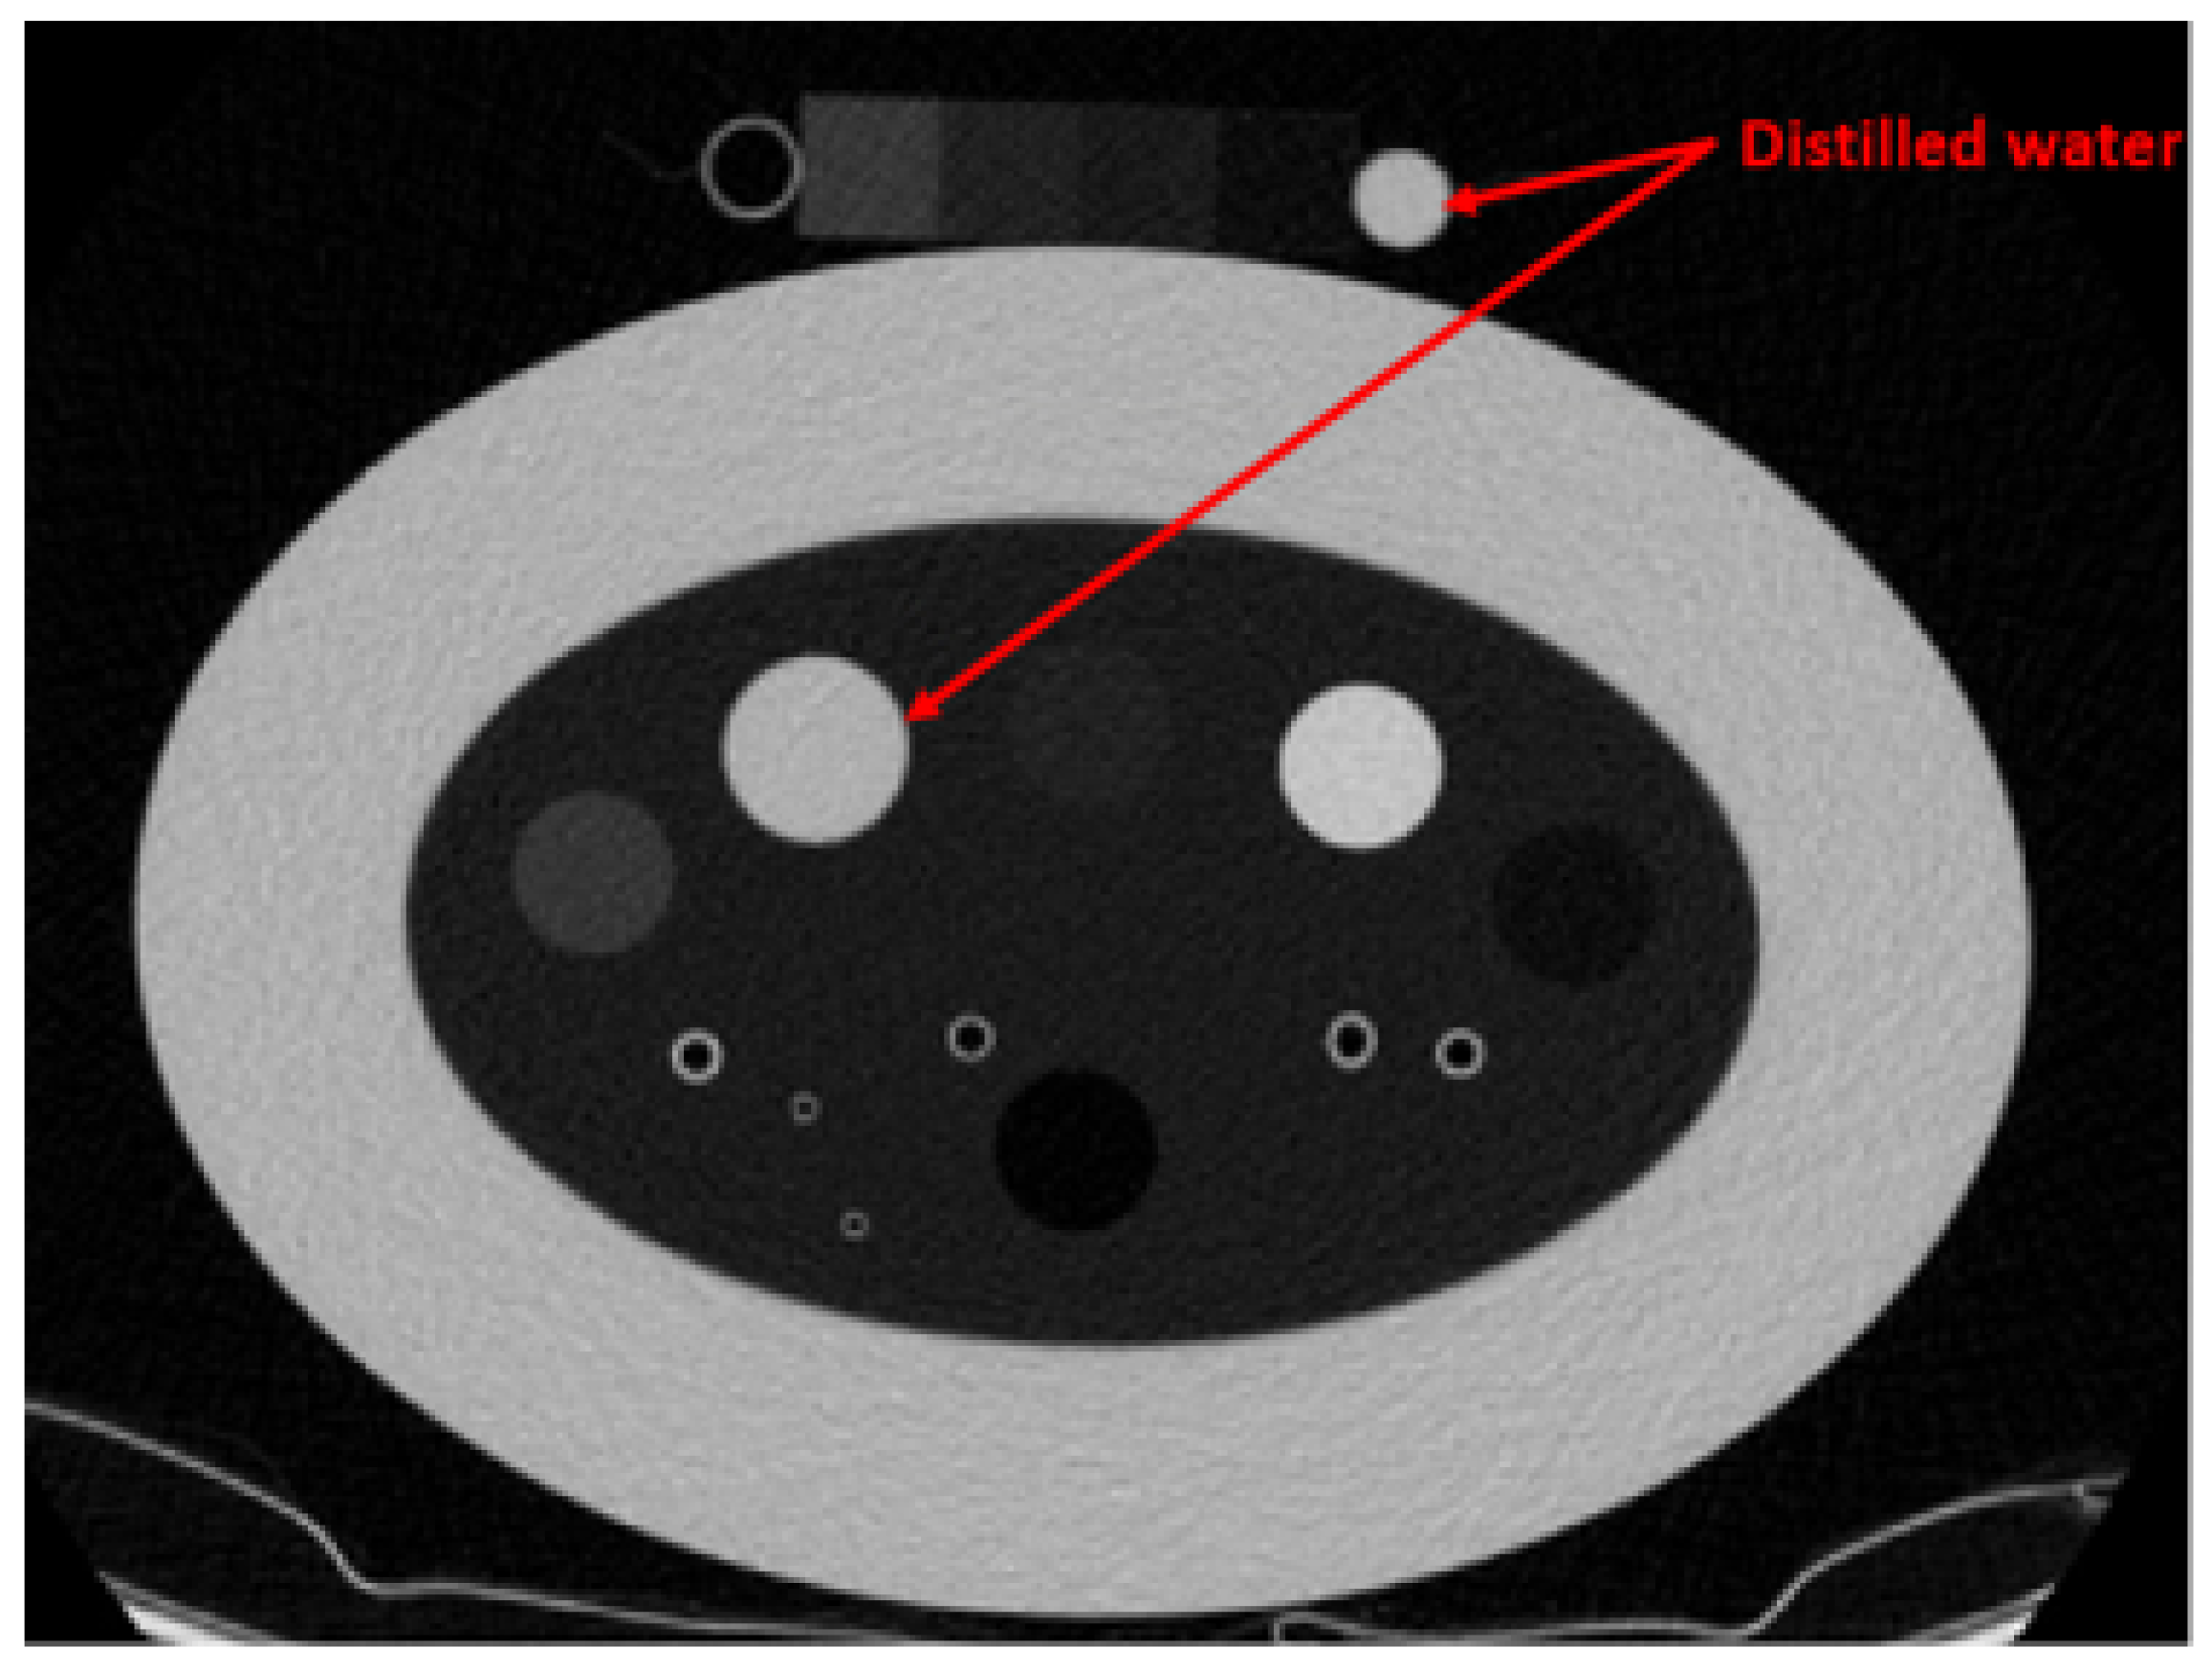

In recent years, several approaches have been proposed to address the limitation of lung CT analysis, aiming to mitigate the effects of lung density variations caused by different acquisition protocols and increase CT number consistencies. Several studies have employed the ComBat CT number standardization algorithm, which evaluates X-ray dose and acquisition protocols to scale the CT numbers based on various statistical models [6,7]. However, the ComBat technique requires parameter analysis prior to the CT number standardization, and the Lung Density Committee provides the scaling information for limited CT scanners and scanning protocols. Chen-Mayer et al. introduced lung CT density standardization method based on the Martinez’s CT number-electron density relation [8]. The method employs the COPD gene2 phantom, which contains various foams within the lung density range, as references (3 foams, air, and water) for CT number standardization. The study demonstrated the effectiveness of the method using 22 CT images acquired with different scanning protocols across four CT scanners. However, using water as a reference decreases the reliability of the standardization process. Water’s density and corresponding CT number can fluctuate due to the external influences, including bubble formation induced by CT scanner vibrations, precipitate accumulation from corrosion within the containing cylinder, and other environmental factors such as pressure and temperature. As illustrated in Figure 1 and Table 1, the average CT number of water, which is expected to be 0 Hounsfield Unit (HU) shows inconsistency even when the same scanner and scanning protocol are used.

Figure 1. CT image of the COPD gene2 phantom with an additionally attached phantom scanned using Revolution 64 with 1.5 mGy dose. The window level is set to [0-1024] HU.

Table 1. Average CT numbers of water in COPD gene2 phantom and attached phantom measured from five repeated scans.

Water (HU)

COPD gene2 PhantomAttached Phantom

1.8−2.7

19.51.7

5.0−7.8

8.92.6

14.7−3.1